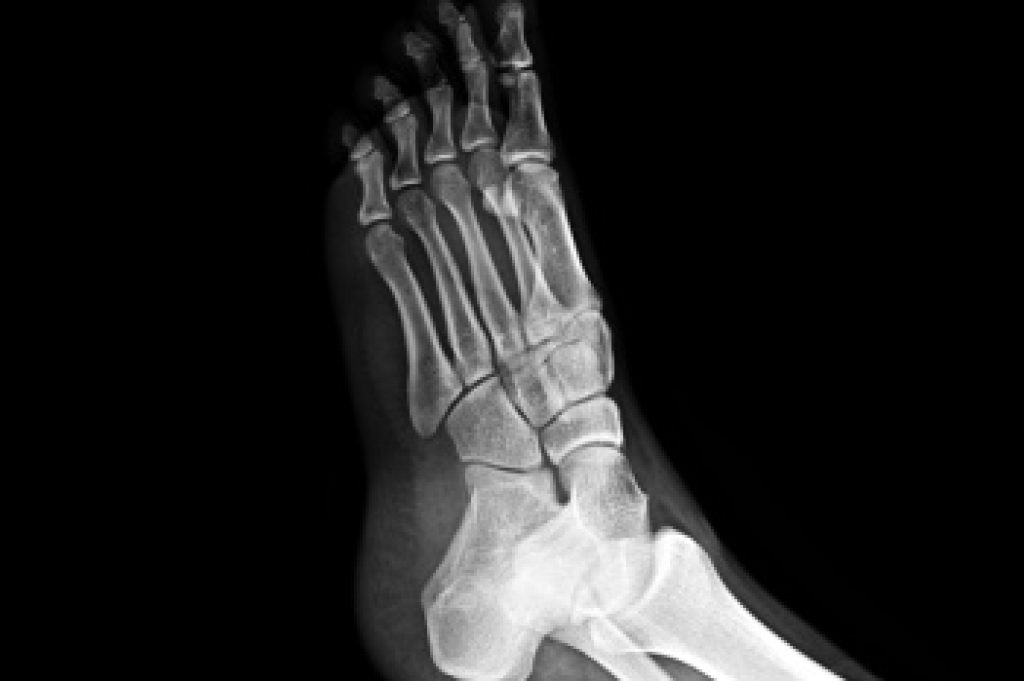

Stress fractures in the feet are hairline cracks in the bone that often develop from repetitive force, rather than a single traumatic event. Stress fractures generally occur in the long bones of the foot, which endure significant impact during walking, running, and jumping. Overtraining, sudden increases in activity, or inadequate rest between workouts raise the risk. Foot structure also plays a role, with flat feet, high arches, or rigid arches contributing to uneven distribution of pressure that can stress certain bones. People with osteoporosis or low bone density are at higher risk, and nutritional deficiencies, such as inadequate calcium or vitamin D, may weaken bone strength. A podiatrist can confirm a diagnosis through examination and imaging, recommend appropriate footwear or orthotics, and advise whether surgery is required in severe cases. If you have symptoms of stress fractures in your feet, it is suggested that you make an appointment with a podiatrist for an exam, diagnosis, and treatment.

Stress fractures are the result of repetitive force being placed on the bone. Since the lower leg and feet often carry most of the body’s weight, stress fractures are likely to occur in these areas. If you rush into a new exercise, you are more likely to develop a stress fracture since you are starting too much, too soon. Pain resulting from stress fractures may go unnoticed at first, however it may start to worsen over time.

Stress fractures do not always heal properly, so it is important that you seek help from a podiatrist if you suspect you may have one. Ignoring your stress fracture may cause it to worsen, and you may develop chronic pain as well as additional fractures.